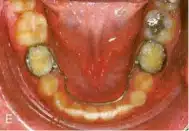

Lingual Arch

نوعی فضا نگهدار است که به بند دندان های مولر وصل می شود و از حرکت مزیالی مولر ها جلوگیری می کند. این وسیله هم در فک بالا و هم در فک پایین قابل استفاده می باشد.